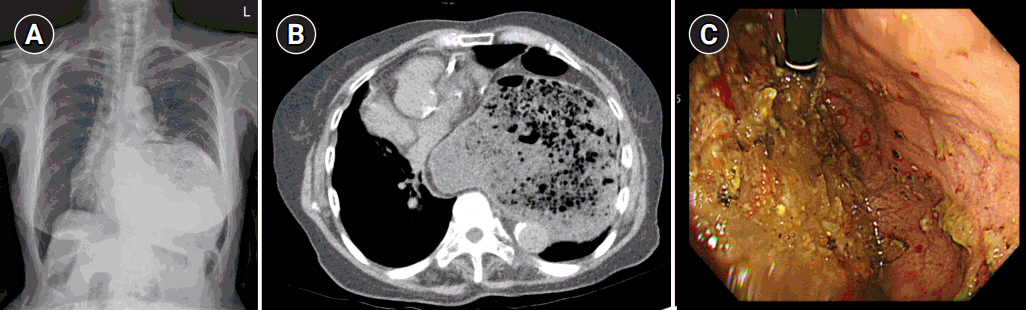

Indocyanine Green Fluorescence-Guided Enucleation via the Serosal Approach for Benign Subepithelial Tumors of the Gastroesophageal Junction

Ji-Hyeon Park, Sojung Kim, Ho Seok Seo, et al.